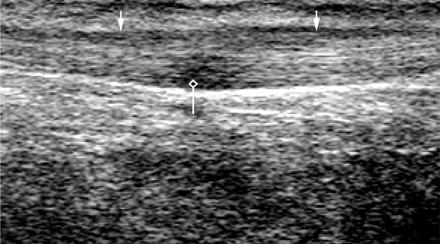

Mirizzi SYndrome

impacted stone in the cystic duct or GB neck

presence of two tubular structures representing the bile duct above the level of the cystic duct

Mirizzi SYndrome

impacted stone in the cystic duct or GB neck

presence of two tubular structures representing the bile duct above the level of the cystic duct